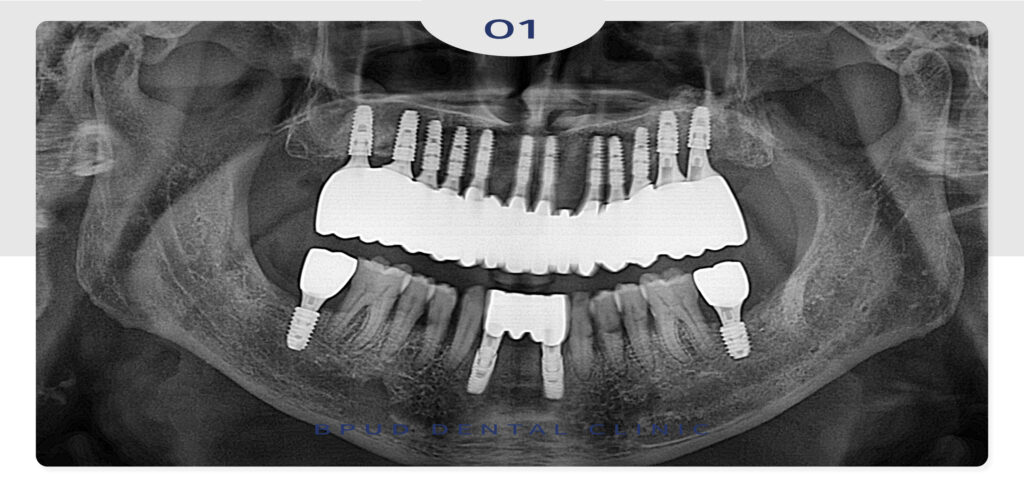

최종 보철물까지 완성한 모습입니다.

환자분께서는 처음부터 전체 임플란트

가능한 많이, 튼튼하게 식립을 원하셨고

안정적인 마무리가 되어 동요도가 심해서

식사도 못하시고 너무 불편하셨는데

부평임플란트를 통해 기능과 심미성 모두를

회복하셔서 매우 만족하셨습니다.